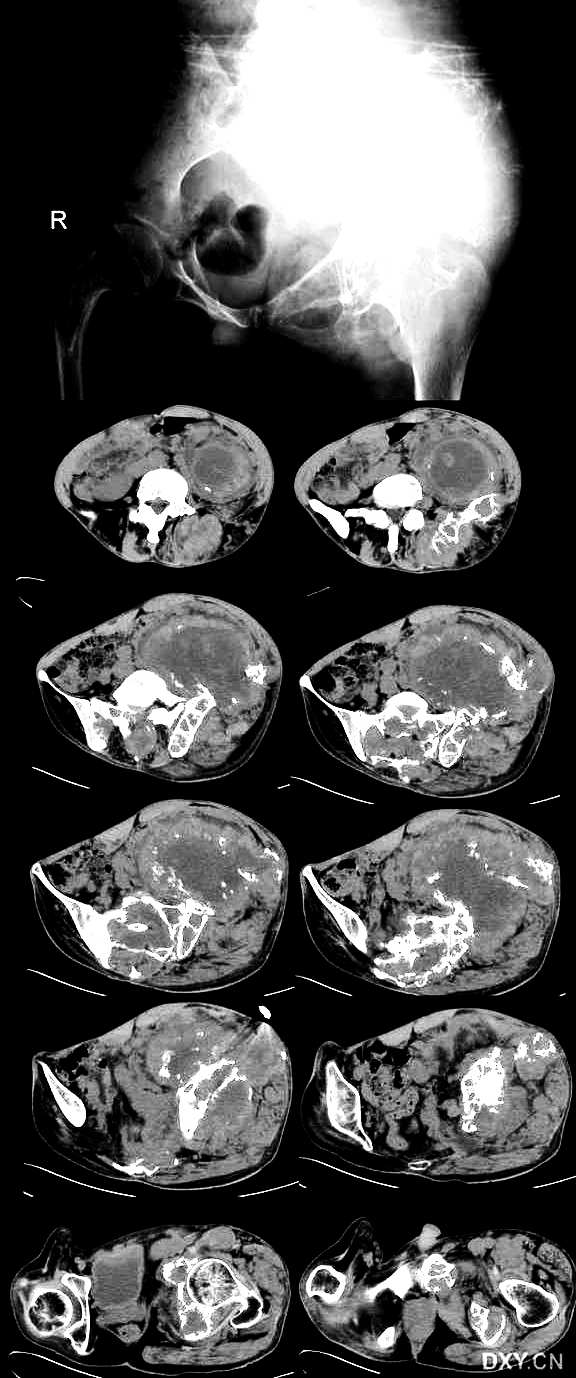

病史:男性,45岁,左髋部疼痛一年余

左侧髂骨见溶骨性股指破坏,边缘模糊,钙化点增多,肿瘤膨胀生长、肿瘤侵入周围软组织中,形成巨大软组织肿块,其内可见散在钙化点。骶骨、左侧髋臼破坏。

意见:软骨肉瘤。

左髂骨溶骨性破坏,边界模糊,肿瘤呈膨胀性生长,可见散在钙化影,并侵犯周围软组织。考虑软骨肉瘤可能性大。

左侧髂骨及骶骨溶骨性破坏,局部形成软组织肿块,以坏死为主夹杂斑点状钙化,残存骨质显示硬化,周围髋部软组织明显肿胀,考虑骶、髂骨结核。

影像表现:左侧髂骨、左侧髋臼及骶骨见溶骨性骨质破坏,其中左髂骨肿瘤呈膨胀性生长,瘤周巨大软组织形成,其内可见散在破坏骨质碎片或钙化点,中间可见液化坏死。

影像诊断:左侧髂骨、左侧髋臼及骶骨恶性骨肿瘤,软骨肉瘤可能性大。

双侧髂骨及骶骨均见溶骨形骨破坏伴软组织肿块,软组织中块内见不规则小的钙化影并可见大范围水样低密度灶。骨质破坏为跳跃性及膨胀性,骨破坏区内及软组织中块内均未见明显环形骨化影(钙化影),软组织肿块对其周围组织推移并可见水肿影。临床提示病程1年。软骨肉瘤不是,因为未见瘤骨及环形软骨钙化影。我考虑骨结核可能性大。

骶骨、左侧髋骨见不规则膨胀性溶骨性破坏;肿瘤侵入周围软组织中,累及盆壁肌及左侧脊竖肌,形成巨大软组织肿块;中央呈低密度,周围呈软组织密度,内见多发小的残存碎骨片;增强后软组织呈轻度强化,中央低密度无强化。

病史:男性,45岁,左髋部疼痛一年余。

影像特点:

1、骨盆多处扁平骨溶骨性破坏并累及左侧股骨上段,无肿瘤骨及钙化;

2、形成巨大软组织肿块;

3、骨破坏区有不规则骨性分隔。

4、临床:男性,45岁,表现左髂部疼痛、肿块一年。